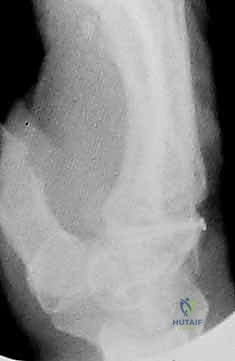

التشخيص هو المرحلة الأهم. الأشعة السينية العادية (X-rays) قد لا تظهر هذه الكسور الدقيقة في البداية بسبب تراكب عظام الرسغ. هنا تبرز خبرة الأستاذ الدكتور محمد هطيف في صنعاء، حيث يعتمد على بروتوكولات تشخيصية عالمية.

- الأشعة السينية بوضعيات خاصة: أخذ صور بأكثر من زاوية لفك تراكب العظام.

- الأشعة المقطعية (CT Scan): المعيار الذهبي لتشخيص كسور عظام الرسغ المخفية وتحديد حجم التفتت والتزحزح.

- الرنين المغناطيسي (MRI): يُستخدم لتقييم الأربطة المحيطة بالرسغ والتأكد من التروية الدموية للعظام (خاصة العظم الهلالي).